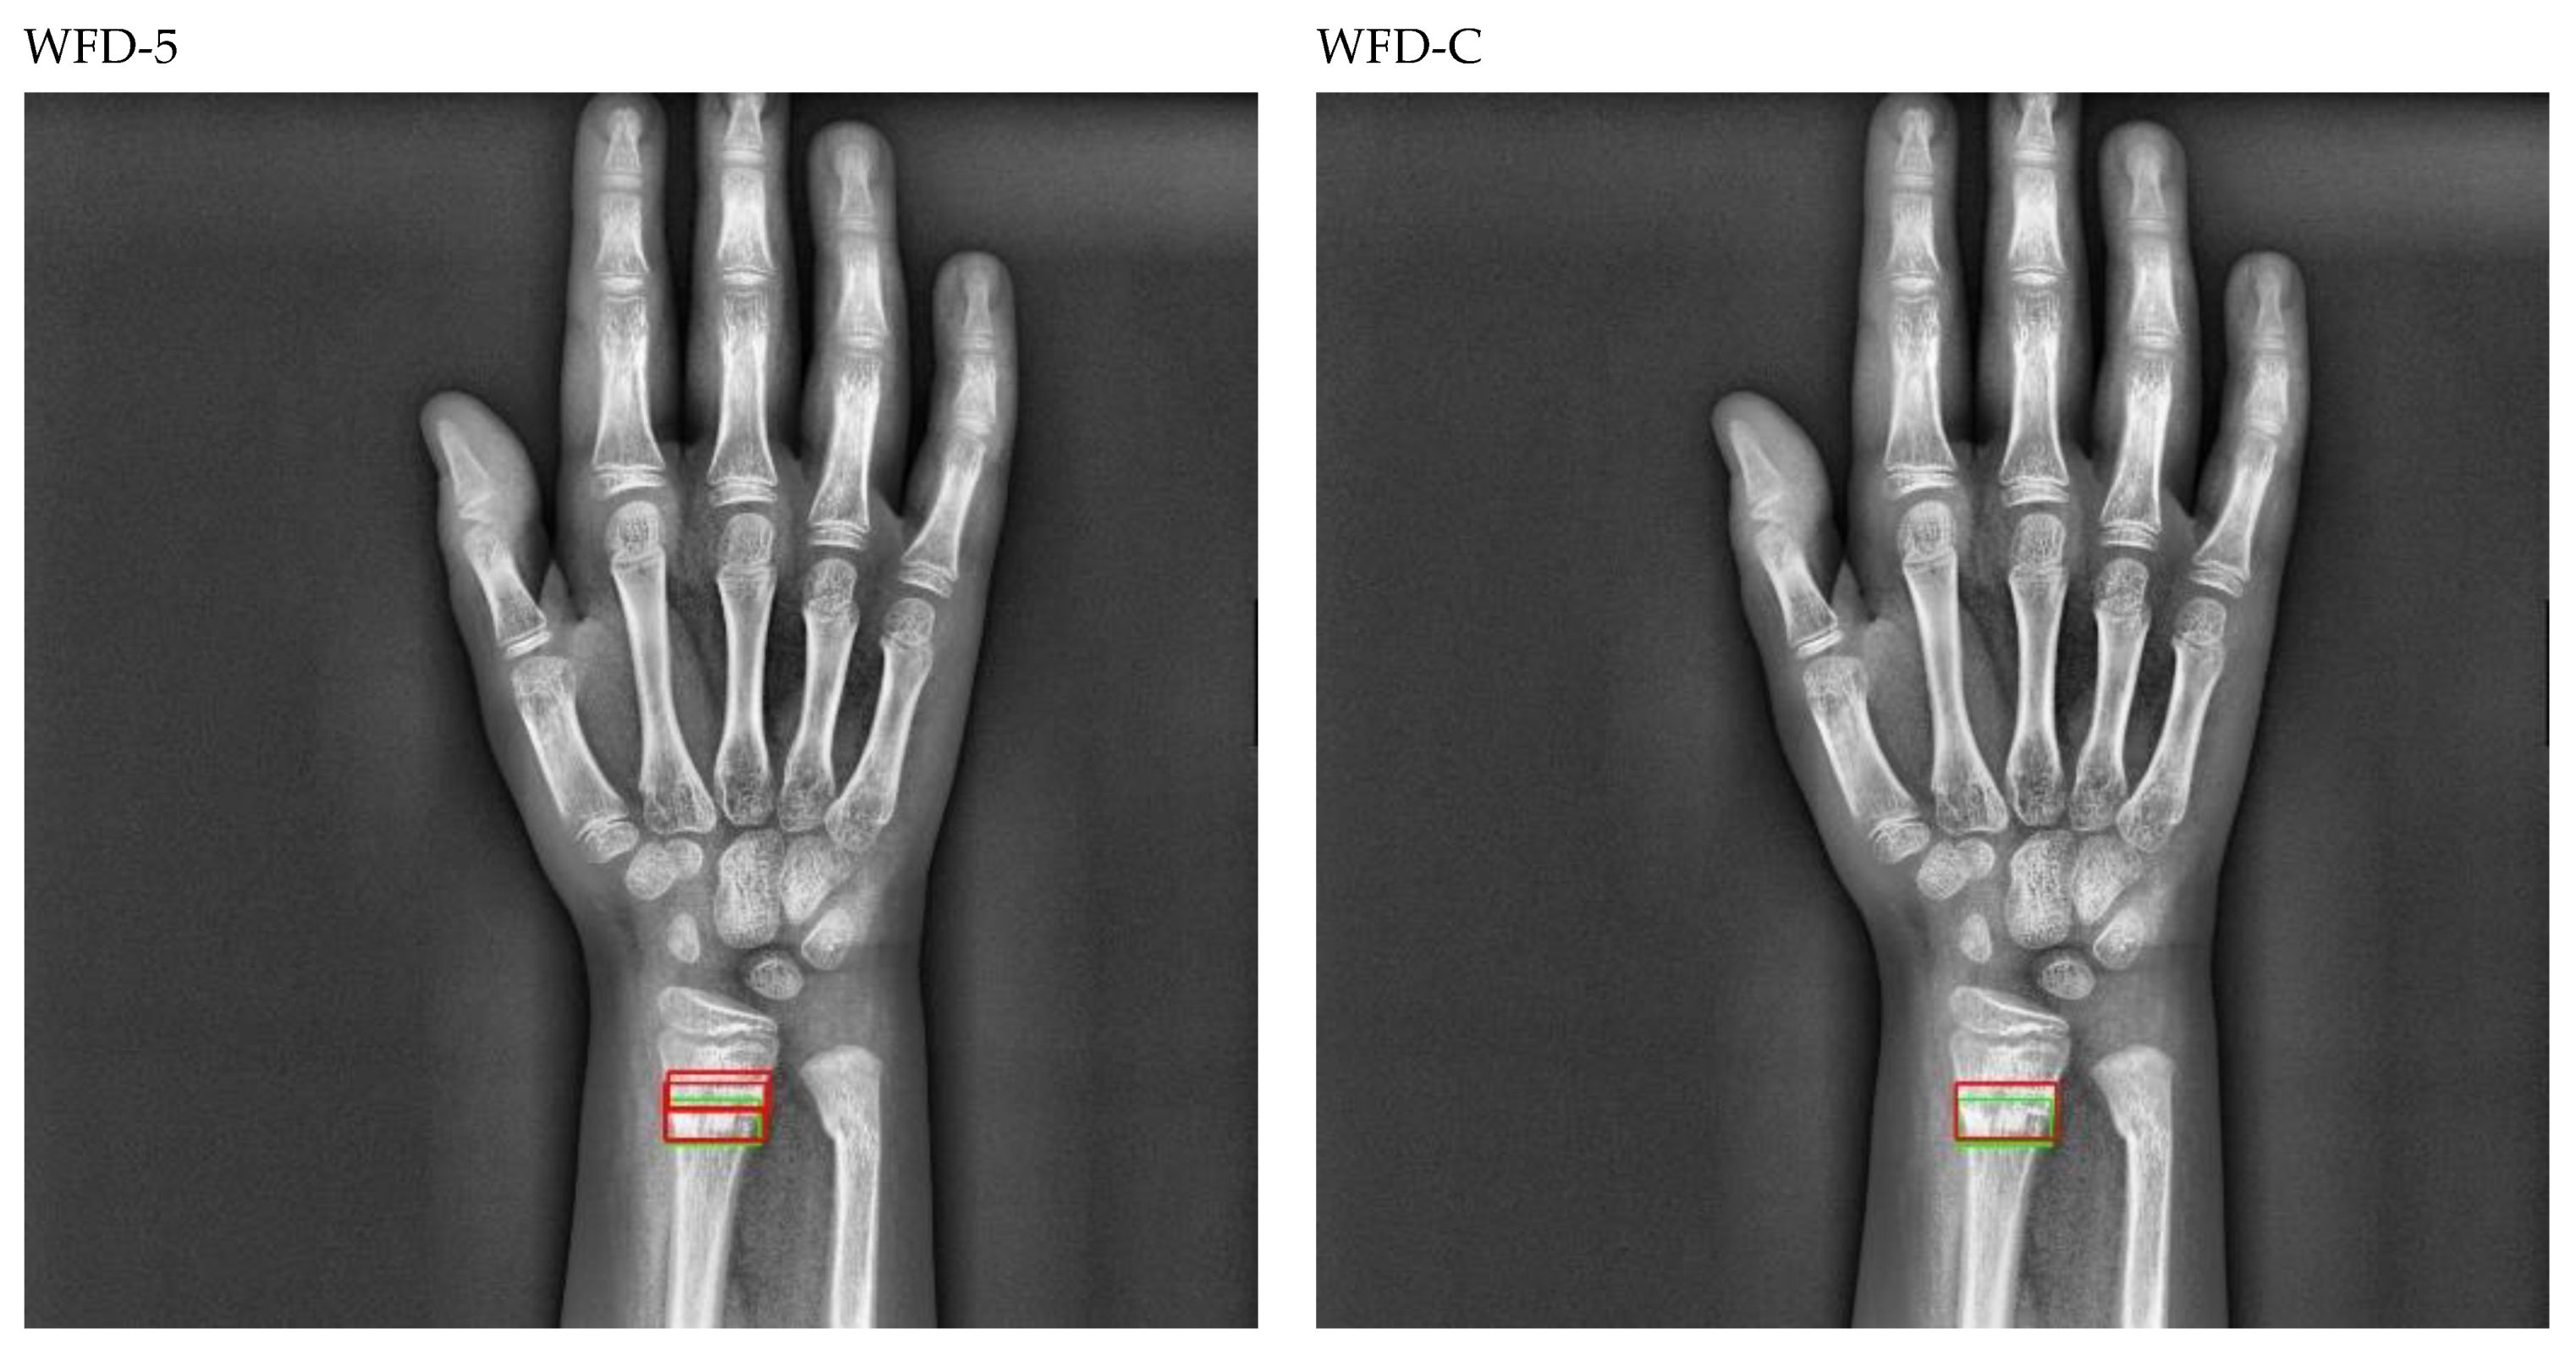

The bounding box outputs achieved from fracture detection performed with ensemble models in wrist X-ray images are provided in Figure 20 and Figure 21 below as a sample for the right/left hand in the dataset.

Figure 20.

Sample of right wrist fracture results [ground-truth bounding box (green), predicted bounding box (red)].

Figure 21.

Sample of left wrist fracture results [ground-truth bounding box (green), predicted bounding box (red)].

The predicted bounding boxes achieved fracture detection suggest that, as shown in the images in Figure 20 and Figure 21, the model that provides the most accurate results that are closest to the ground-truth bounding boxes is the WFD-C ensemble model developed in this study. Moreover, the examination of the number of predicted bounding boxes reveal that the model with the lowest number on the test data is also WFD-C. For the fracture detection in wrist X-ray images, Figure 22 below shows the total number of predicted bounding boxes obtained for each model on the test dataset as the result of the fracture detection performed with a total of 26 deep learning models, six of which are ensemble models.